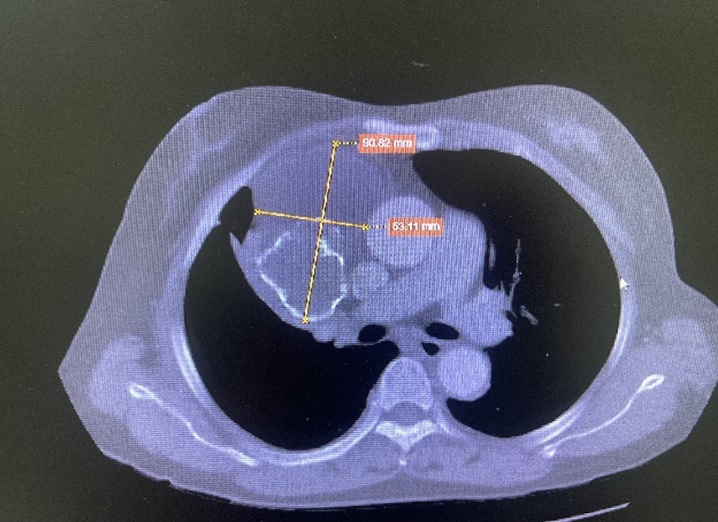

Tỷ lệ mắc của u trung thất trong cộng đồng nói chung vào khoảng 1/100.000 người/ năm. U trung thất thường gặp bao gồm: U tuyến ức, u tế bào mầm, nang khí - phế quản, u thần kinh trong trung thất, u lym-phô… các u này chiếm khoảng trên 60% tổng số các trường hợp, trong đó u lành tính chiếm phần nhiều, thường ít có triệu chứng lâm sàng. U trung thất có thể xuất hiện ở tất cả các lứa tuổi, nhưng thường gặp hơn ở người trẻ và trung niên. Thông thường u trung thất được chẩn đoán qua khám sức khỏe định kỳ khi không có biểu hiện lâm sàng hoặc ở giai đoạn muộn khi đã có hội chứng chèn ép - thâm nhiễm điển hình.

Từ nhiều năm nay, khoa Ngoại Thần kinh - Lồng ngực, Bệnh viện Đa khoa tỉnh Bắc Ninh đã triển khai thường quy kỹ thuật phẫu thuật nội soi điều trị U trung thất. Việc thực hiện thành công kỹ thuật này là một bước tiến lớn trong lĩnh vực ngoại khoa về Lồng ngực, giúp người bệnh được thụ hưởng kỹ thuật hiện đại, chất lượng chăm sóc sức khỏe tốt ngay tại địa phương mà không phải đi xa.